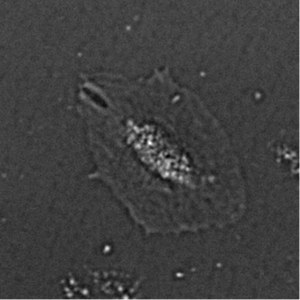

As it was noticed Fig.2(d) is example of low accuracy segmentation. The highly contrast cell core on this image attracts attention, while cell body and boundaries remains shattered. This contrast difference caused by cell morphology since cell itself has no more lens shape and changes to sombrero-hat shape affecting on contrast distribution. Fig.6 demonstrate changes of cell image during processing. As it seen there is high contrast core(actual cell nuclei zone) and almost invisible by eye body of cell with contrast same as in background when it seen by eye. After filtration with G-neighbor and Kuwahara it is appear to became more contrast. However because of values for binarization applied globally for rest of images in sequence it produce false negative recognition 7.

Figure 6: Contrast enhancement as result of filter applying on images of Frame 15.